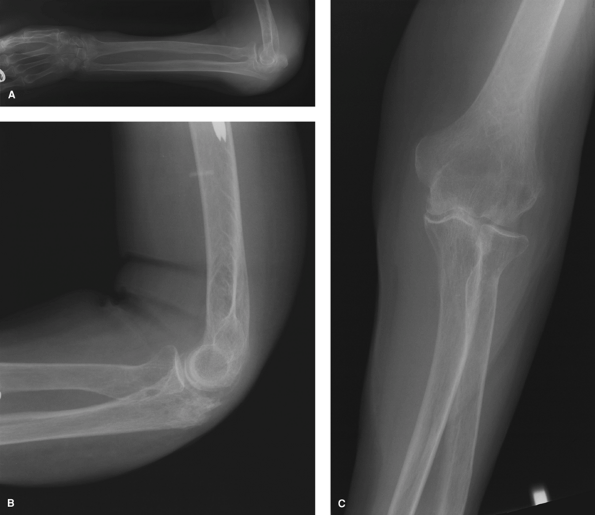

Figure 56-4

This 84-year-old right hand–dominant woman experienced a syncopal episode and fell down the stairs at home. She sustained concomitant fractures of the left proximal humerus, left distal radius, left ulnar styloid, and a fracture of the left olecranon (A) treated with excision of the proximal fragment (B and C). At 6 months postoperatively, she was painfree and her range of motion in the flexion extension arc was from 20 to 135 degrees; pronation was to 70 degrees and supination was to 70 degrees. |

for nonunions, in those with poor soft tissue viability, for

avulsion-type extra-articular fractures, and in cases with severe

comminution as in Mayo type IIB, or rarely, type IIIB fractures (Fig. 56-4).